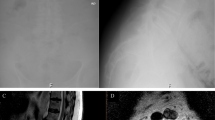

After successful general anesthesia, patients were placed in the prone position, and two sets of spinal UBE instruments were routinely prepared. The patient was placed in the prone position, and the bed surface was adjusted to make the target intervertebral space as vertical as possible relative to the ground. The lesion site and the corresponding intervertebral space level were determined by fluoroscopy (Fig. 1, AB). Two operators treated one segment on each side of the patient, The two surgeons are from the same center, the same diagnosis and treatment team, and are doctors of the same level and level. and routinely incised with a sharp knife at the inner edge of the pedicle 1 cm from the spinous process and 1.5–2 cm above and below the intervertebral space. The endoscope and working channel were determined based on the surgeon’s left and right-hand operation habits (Fig. 1, AB). Operator’s station (Fig. 1, C); a serial dilator was used for insertion into the lamina. The working cannula was placed after removing the dilator. The vertebral plate was opened in the working channel for operation. Figure 1,D shows the intraoperative anteroposterior fluoroscopic positioning view. Based on the location of the lesion, ipsilateral hemilaminectomy was conducted using a drill and a rongeur to expose the deep part of the ligamentum flavum. The drill and the rongeur were used to remove hypertrophic facet joints and lamina. Then, the ligamentum flavum and the dural space were explored using a blunt hook to ensure that there was no adhesion. The ligament and nerve were stripped using a curette and a rongeur to decompress. For contralateral decompression, the midline of the spinal canal was first determined using a high-speed drill. The range was then adjusted from the middle. Partial resection of the base of the spinous process prevented it from obstructing the operating range to ensure adequate working space. After exposure, the ligamentum was dissected from the contralateral lamina and cut. The contralateral approach was performed dorsally to the dura, keeping the ligamentum flavum intact. The craniocaudal laminotomy was used for additional decompression. Partial resection of the contralateral superior articular process was conducted to preserve the integrity of the facet joint. After complete decompression of the bony structure, the hypertrophic ligamentum flavum was resected to fully decompress the nerve structure. The endpoint of decompression was the outer edge of the bilateral nerve roots10. Bilateral consistent operation was conducted. Drains were placed bilaterally.

A: Determining the position of L3/4/5 pedicle of vertebral arch and target point by body surface fluoroscopy; B: Determining the position of intervertebral space by simultaneous fluoroscopy of two segments; C: standing position of the operator; D: the intraoperative anteroposterior fluoroscopic positioning view.